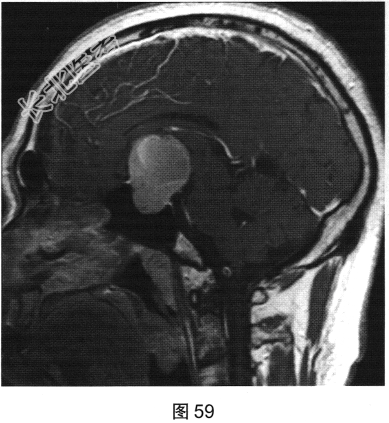

- 多项选择题2.[提示]患者行垂体MRI检查,见图55~图59。患者MRI检查可见哪些阳性影像学表现( )

A、矢状位增强扫描显示垂体及垂体柄显示不清

B、冠状位T1WI上呈等高信号

C、矢状位T1WI上视交叉抬高

D、冠状位T2WI上呈等高信号

E、矢状位T1WI上垂体显示不清

F、冠状位T1WI上可见钙化信号影

G、冠状位增强扫描显示实性部分明显均匀强化

H、MRI示鞍区囊实性占位性病变

I、冠状位增强扫描显示双侧海绵窦受侵